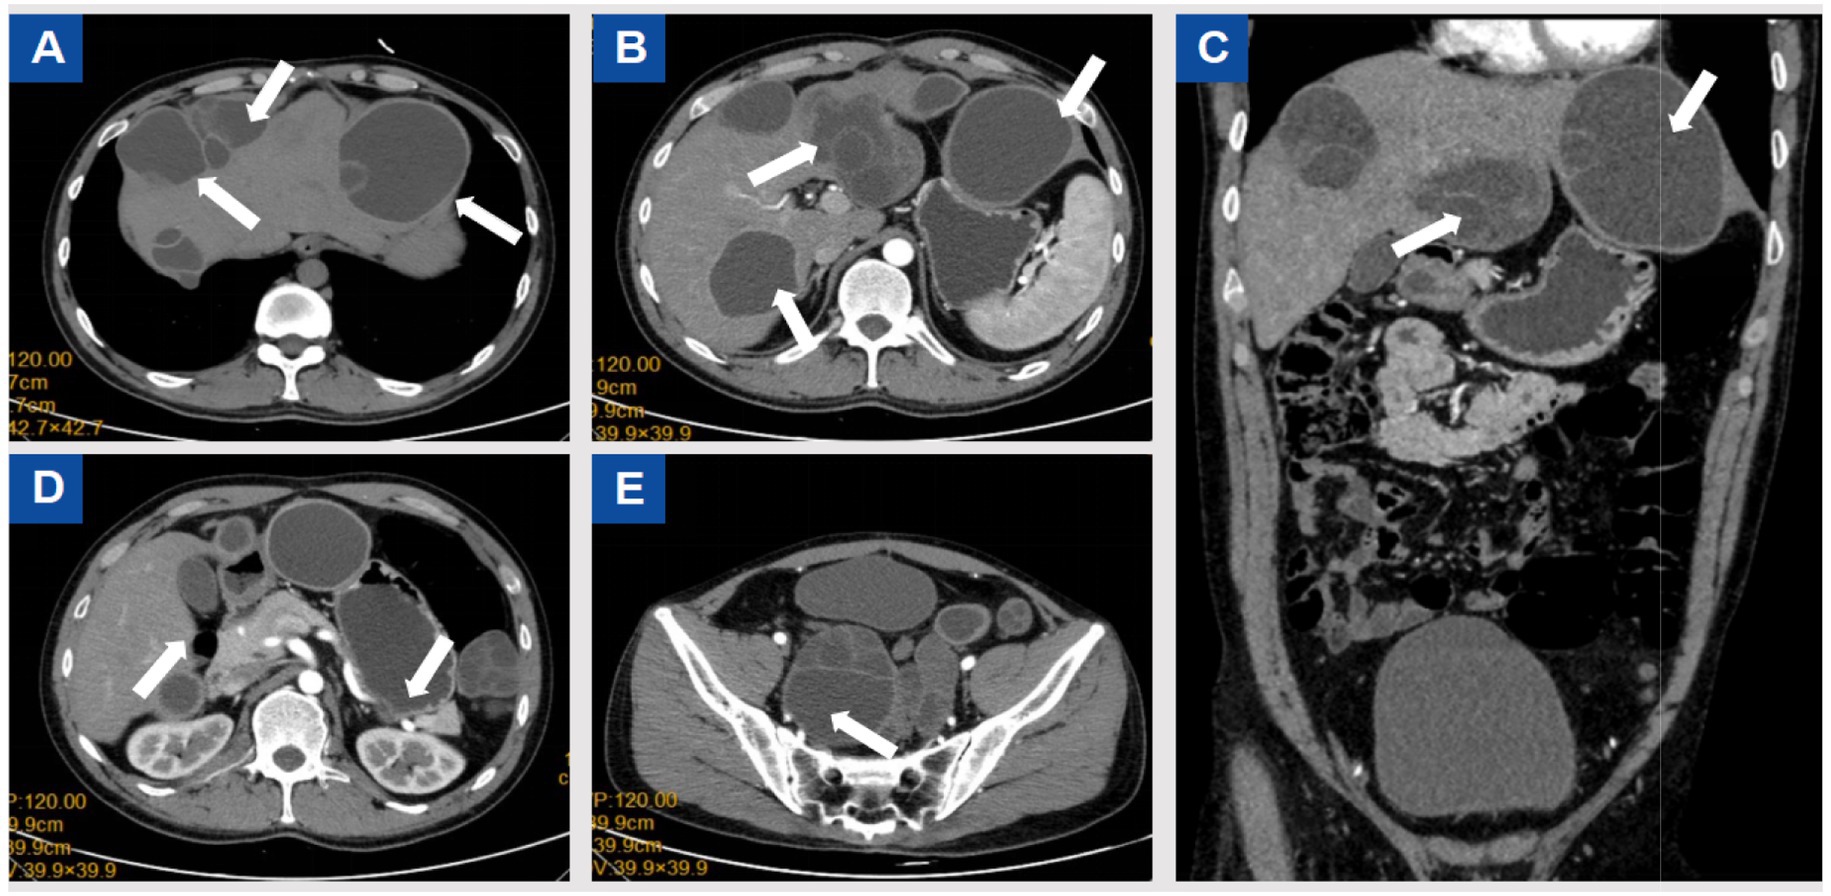

Cranial CT was unremarkable. Chest and abdominal CT revealed multiple small nodules in the posterior basal segment of the left lower lung and the middle lobe of the right lung, with mild bronchiectasis and infection in the right middle lobe, as well as a small pericardial effusion. Multiple cystic lesions were observed in the liver, abdominal cavity, and pelvic cavity, some of which compressed the left ureter, causing mild hydronephrosis. The cystic lesions included localized small cyst clusters and the typical “floating membrane sign,” with several lesions extending beyond the hepatic contour. The largest left hepatic lesion measured approximately 88 × 77 mm, the right S8 lesion approximately 95 × 75 mm, the inferior splenic margin cyst approximately 40 × 76 mm, a minor lesion anterior to the greater omentum measured 23 × 28 mm, and the largest pelvic multilocular lesion measured 109 × 103 mm. All cysts demonstrated internal septations, as shown in Figure 1. Due to long-term lack of follow-up, early symptoms were atypical, resulting in delayed diagnosis. Using WHO-IWGE criteria, the main lesions were staged as follows: the largest left hepatic lesion demonstrated detached membranes consistent with CE3a; the right S8 lesion with daughter cysts and internal septations corresponded to CE3b; and the inferior splenic margin cyst and the pelvic multilocular lesions demonstrated multivesicular architecture consistent with CE2. These stage assignments informed the decision for open surgical resection combined with perioperative scolicidal measures.

Figure 1

Preoperative CT scans. According to the WHO-IWGE classification, the hepatic cysts corresponded to CE2–CE3b stages, while the splenic and pelvic cysts were CE2.